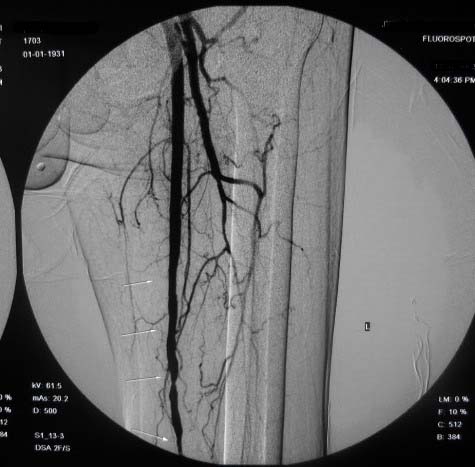

左下肢:

右侧股浅动脉上、中段多处狭窄,下段闭塞。左侧股浅动脉多处狭窄,国动脉起始部狭窄。可以用球囊扩张配合动脉内溶栓或股浅动脉支架置入。多为糖尿病所致。

双侧股动脉及腘动脉多发狭窄,右股动脉下段闭塞并侧支形成。病变较广泛,球囊可试试,如病人经济不好,最好还是以药物治疗为主。个人意见。